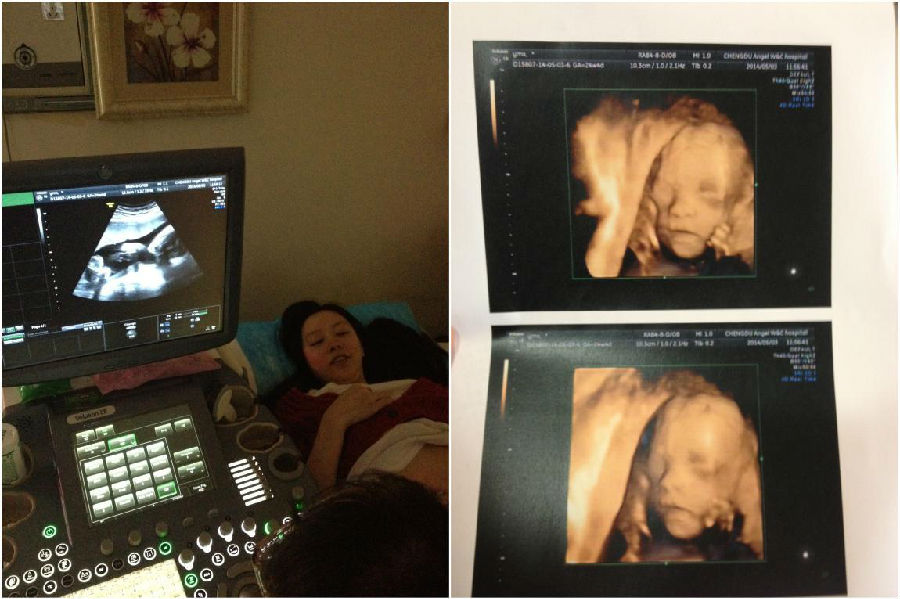

201453日。到了打四位彩超的日子,宝宝照出来很斯文,妈说像胖妹。胖妹说像我,宝宝其他都很正常,但是医生说宝宝肺动脉瓣回流血流,有可能是先天性心脏病,而且这个情况不多见。建议我们做产前检查。在妈妈爸爸面前,胖妹儿怕他们担心,还稳起说没啥子问题。妈妈爸爸一走,胖妹儿就哭了。一边查资料,一边在她的孕妈群里面咨询。我也一直在开导胖妹儿,宝宝还小,等我们复查的时候就差不多长好了。胖妹儿只是哭,我心里又何尝像开导她那么轻松,“像有石头压在心头”这个比喻真贴切。

201467日。我一直是信春哥的,也坚信生儿生女都一样。但是胖妹儿对宝宝的性别非常好奇,又不好意思问医生,于是这个艰巨的人物交给妈妈了。下面是打B超或彩超的问题:“医生,我们需要准备弟弟还是妹妹的衣服。”“医生,娃儿长的像爸爸还是妈妈。”“医生,娃儿长得帅还是漂亮。”语气之委婉,用词之恰当,目的之明确。可惜成都三甲医院根本不吃你那一套。于是今天还是老老实实回广汉来找熟人···儿子,我以后不用担心你在外面被那些青钩子娃儿占便宜了。